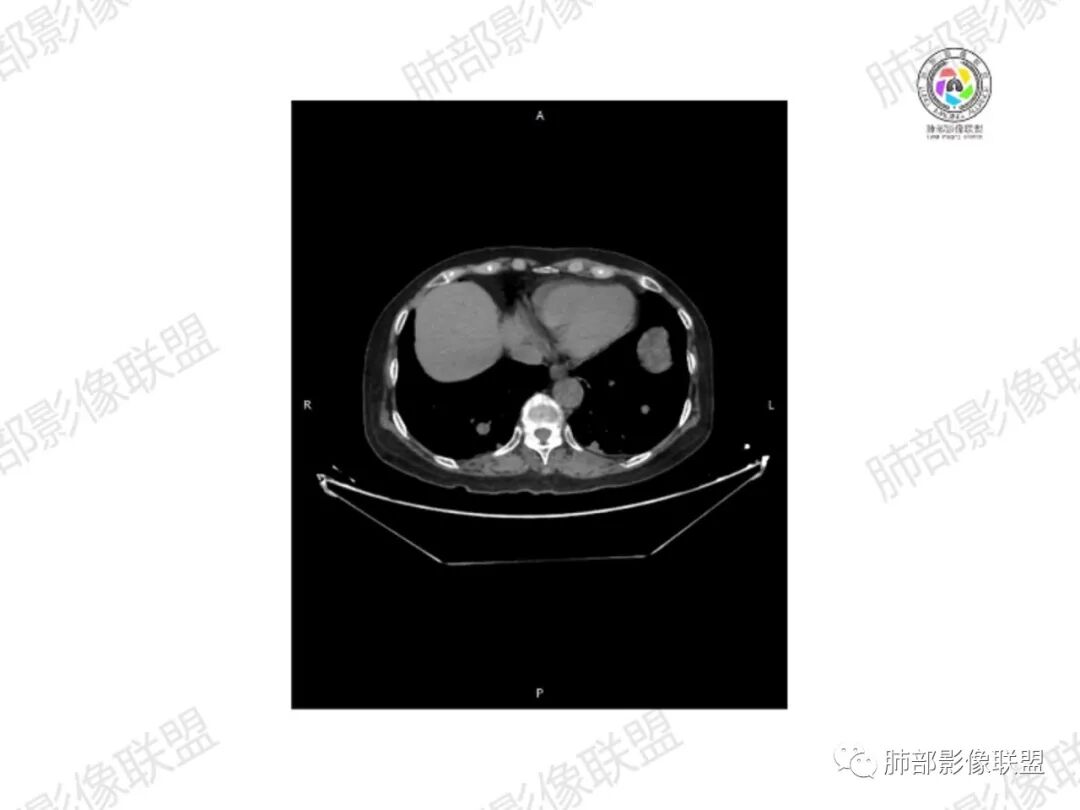

5.双肺多发类圆形结节影,边界清楚,随机分布,其间多见钙化密度影。

6.双肺门及纵隔未见肿大淋巴结。

3.双肺病灶符合转移瘤,伴有中央部分钙化者也以骨肉瘤转移较为多见。